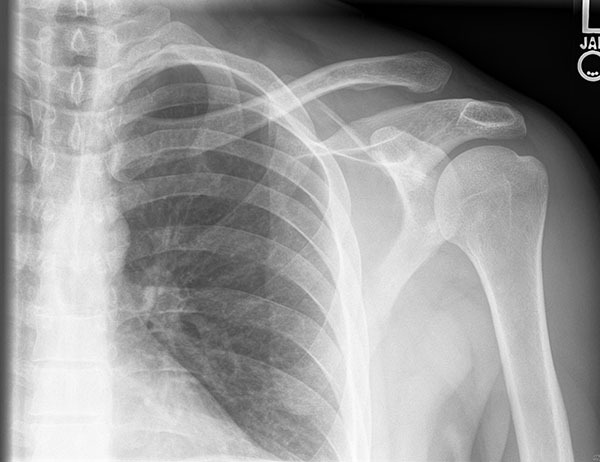

Physical examination in poster dislocations typically shows anterior shoulder flattening with a posterior prominence and an inability to rotate or abduct externally. The arm may be locked in an internally rotated position. Plain film imaging may appear normal or reveal a “lightbulb” appearance of the humeral head; however, the trans-scapular Y view should demonstrate a humeral head posterior to the glenoid fossa. (See Figures 3 and 4.) A Velpeau view may be obtained if the patient cannot comply with a trans-scapular Y.44

Figure 3. Posterior Dislocation Anteroposterior View |

![]() |

Courtesy of J. Stephan Stapczynski, MD. |